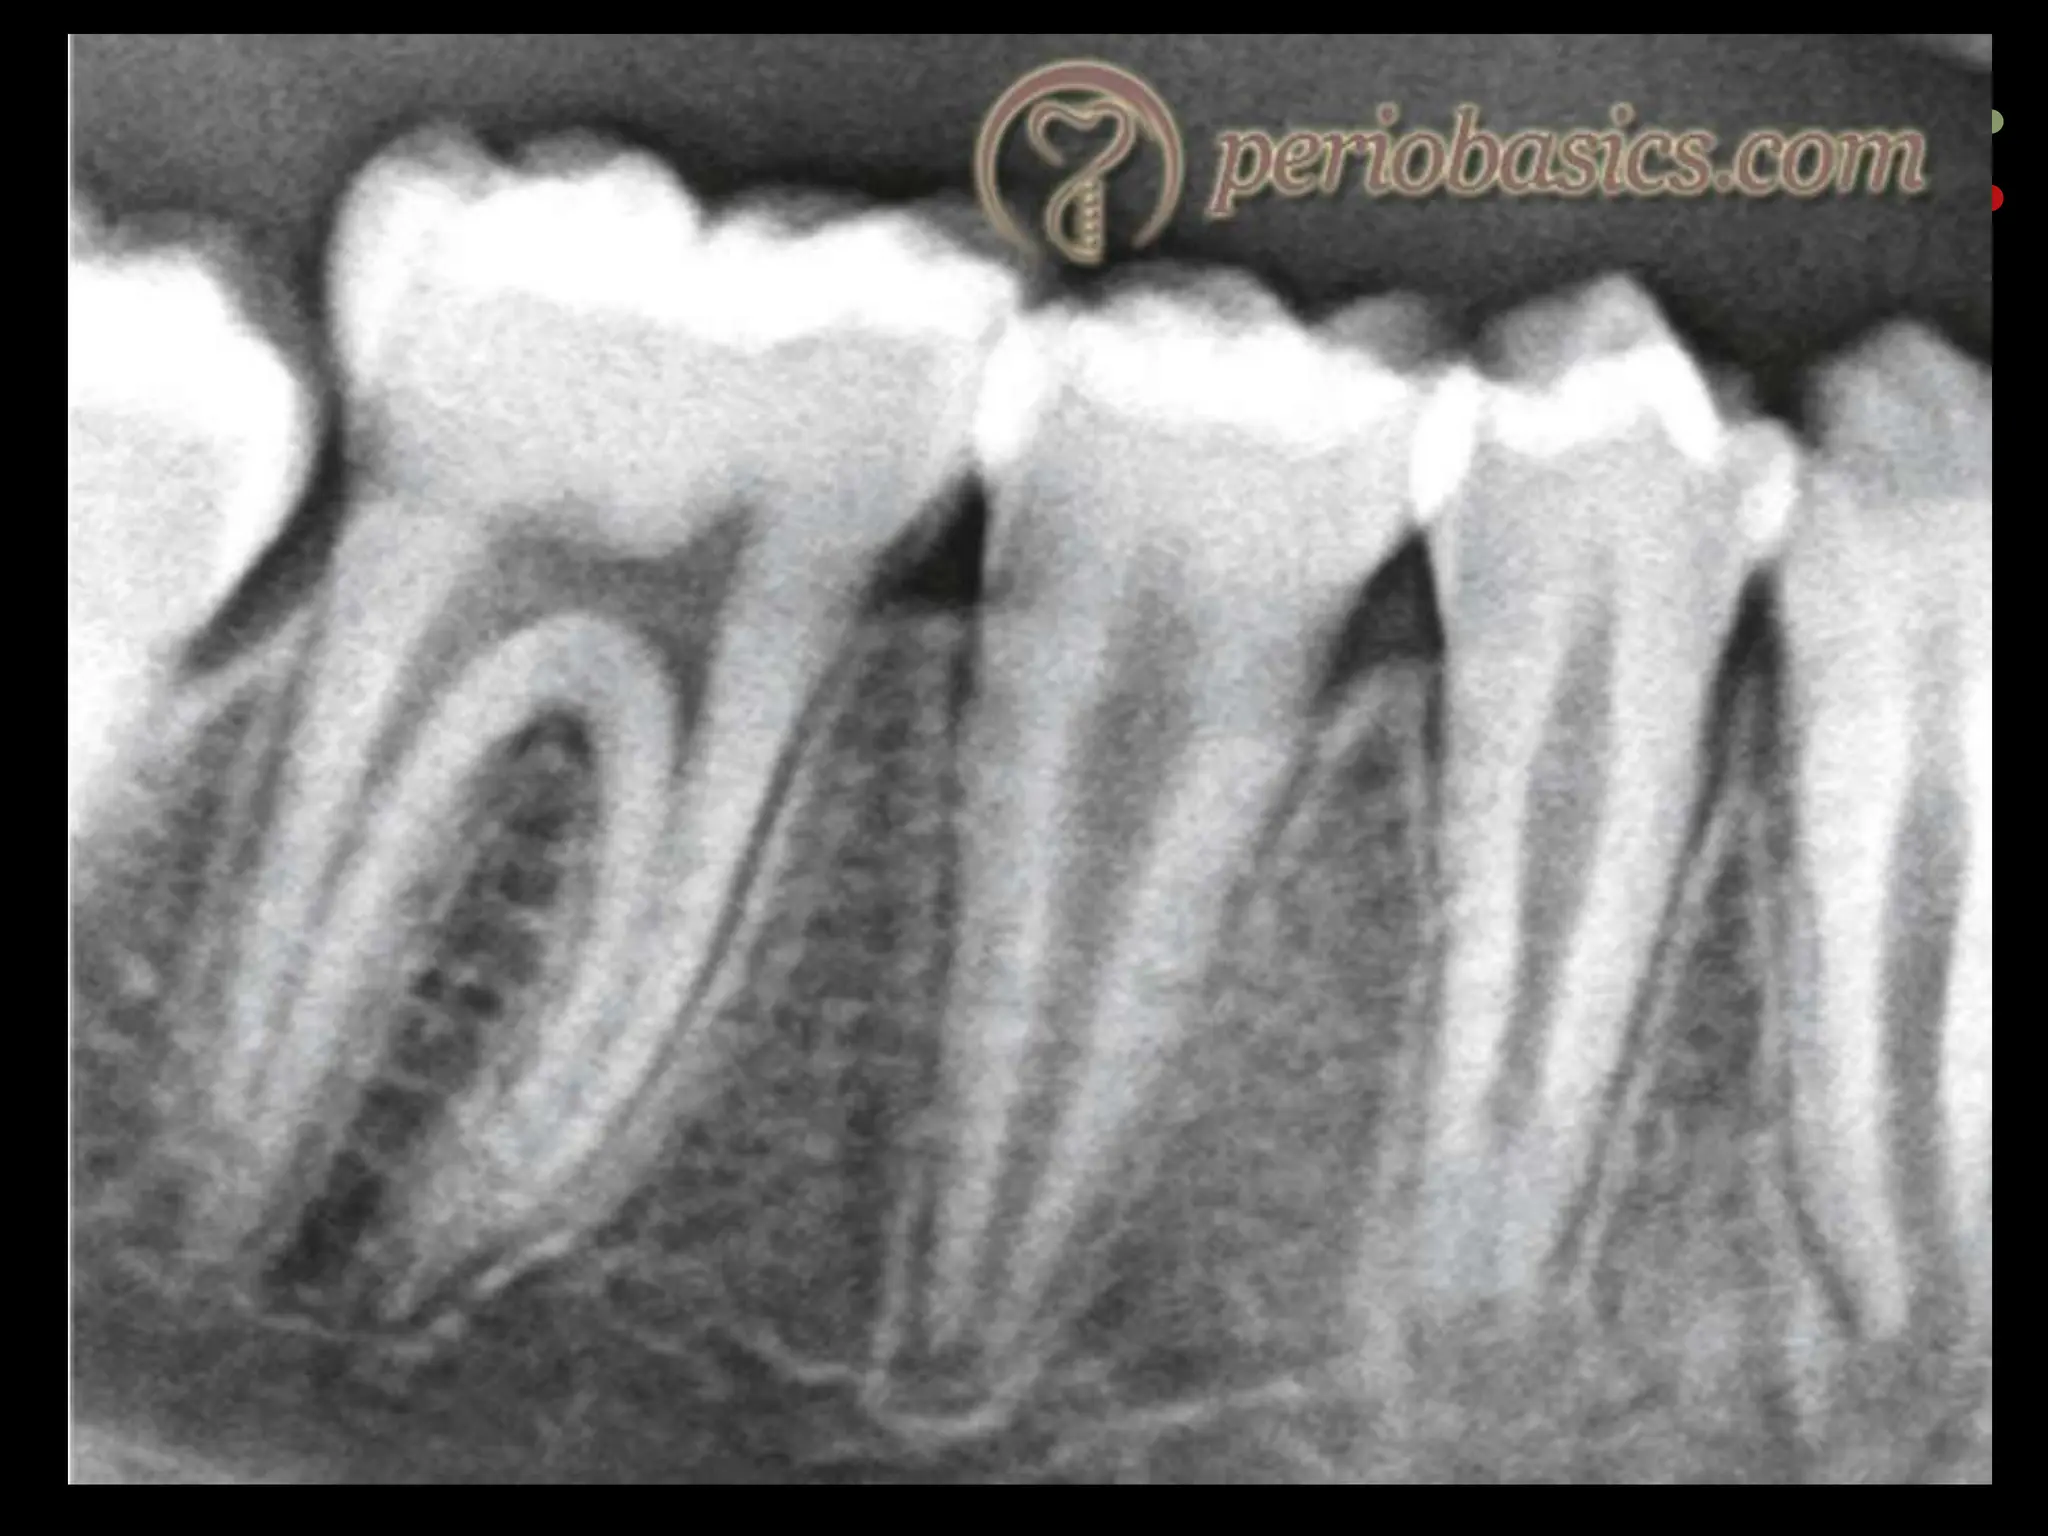

Digital subtraction radiography

77

Digital subtraction radiography Subtraction in digital radiology is another image enhancement method with purpose to produce two radiographs of the same area in the mouth at the different time intervals.  The first image can be subtracted from the second one to identify changes that may have occurred during a certain time period. Minimal changes in loss or gain of hard tissue can be detected using this technique, otherwise undetectable by visual examination and traditional radiography. 77